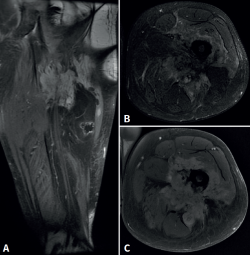

Figura 4. Resonancia magnética del fémur izquierdo. A: corte coronal en secuencia STIR, con masa de partes blandas de gran tamaño con afectación diafisaria femoral; B: corte axial en secuencia T2, con masa heterogénea con áreas de necrosis central; C: corte axial en secuencia T1 con supresión grasa, con compromiso del trayecto del nervio ciático por la masa tumoral.